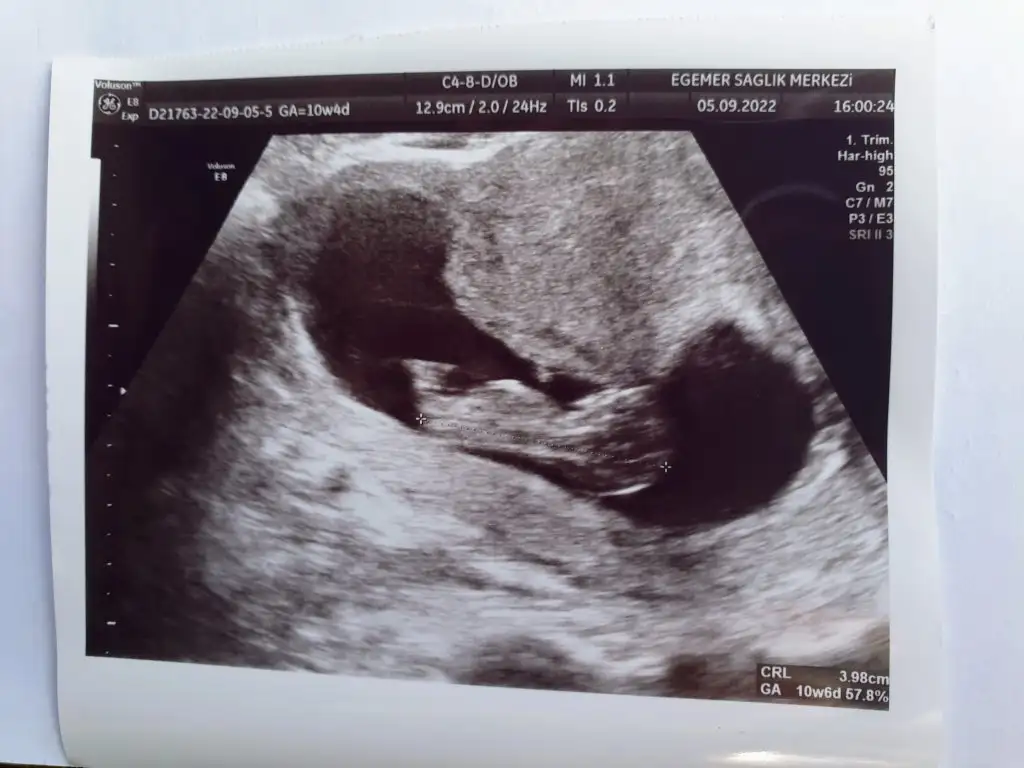

Doktorumdan geliyorum, benim bebek 2 gün geride çikarken, bugün 2 gün önde çıktı.

Birde cok hareketli değildi sanırım ki doktor ultrason kamerasını biraz bastirdi karnımda titretti falan, neden öyle yapti sizce ya? Herşey yolunda dedi ama benim İçim rahatsız kizlar ya

Eki Görüntüle 3125185